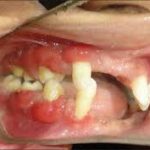

Palmarplantar hyperorthokeratosis with precocious periodontal destruction in the primary and permanent dentition. Thought to be the result of homozygosity of autosomal recessive genes.

Papillon–Lefevre syndrome is an uncommon genetic condition that impacts the skin and gums. It leads to regions of dense, fissured skin. Furthermore, from an early age, the gums become susceptible to infections. Severe gum conditions result in the early loss of milk teeth, and by the age of 20, it might lead to the loss of all adult teeth.